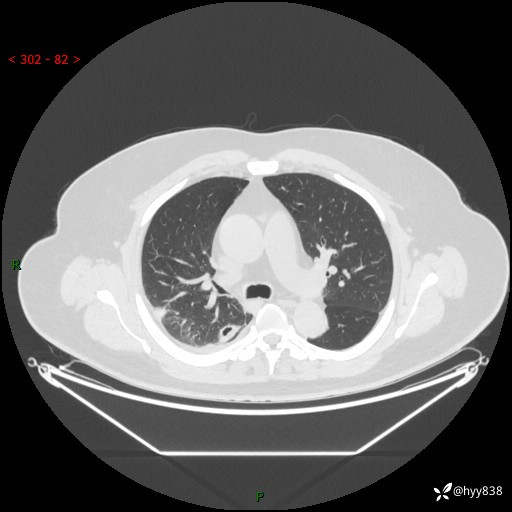

性别:男

年龄:48岁

简要病史:发热来诊(门诊病人)

胸部CT平扫